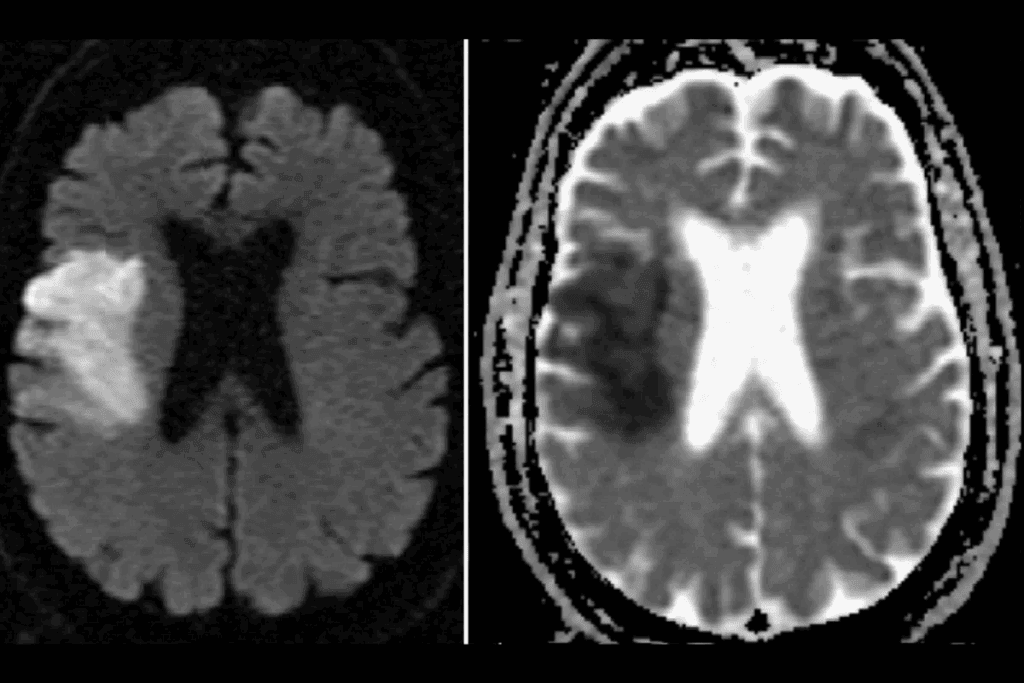

Imaging Studies

Imaging tests are key in finding cerebral hyperperfusion. CT scans, MRI, and Transcranial Doppler ultrasound help see the brain’s blood vessels and blood flow.

| Imaging Technique | Use in Cerebral Hyperperfusion Diagnosis |

| CT Scan | Helps in identifying hemorrhage or edema |

| MRI | Provides detailed images of brain tissue and blood vessels |

| Transcranial Doppler Ultrasound | Measures blood flow velocity in the cerebral arteries |